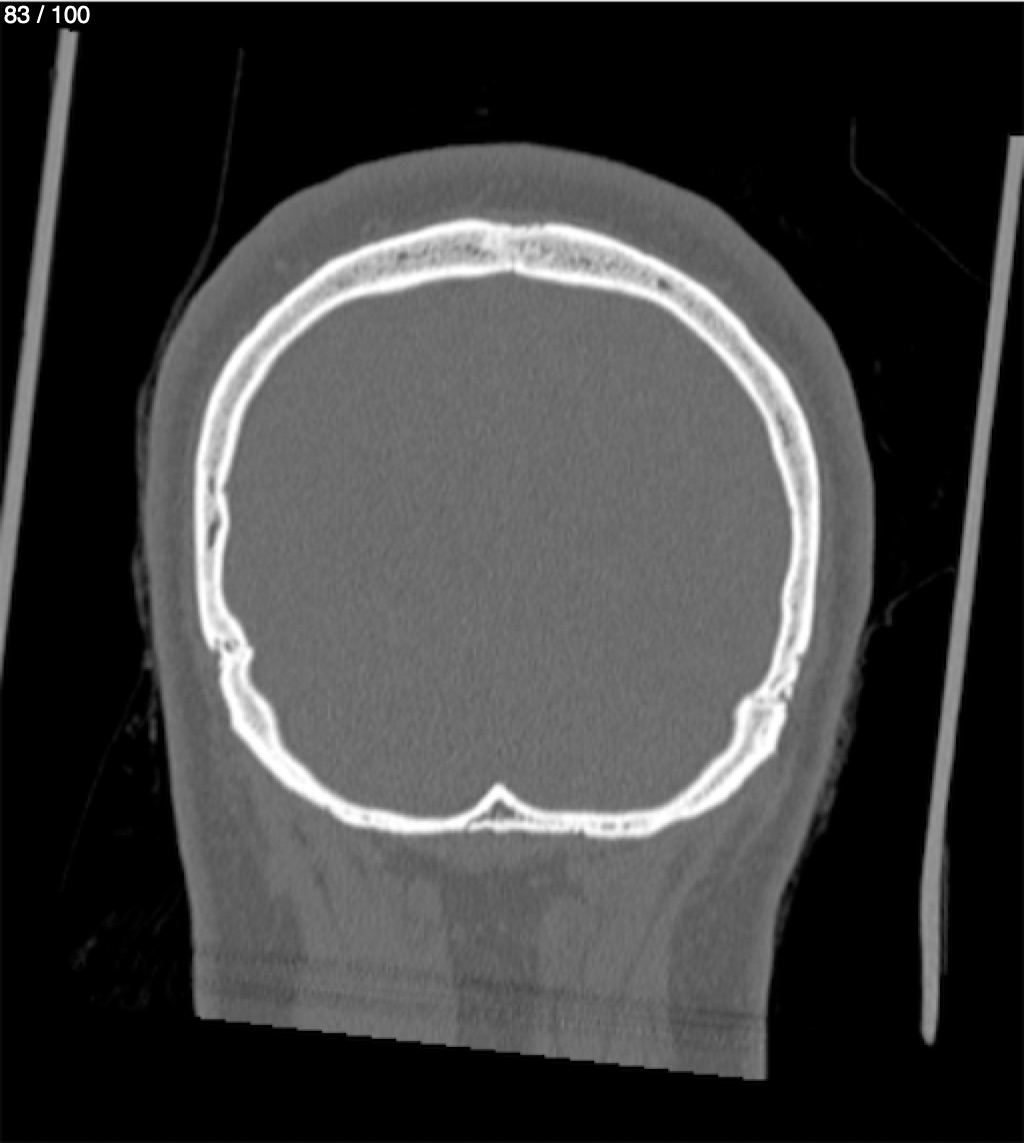

Reybet Garcia Fuentes 30A - T.C Craneo